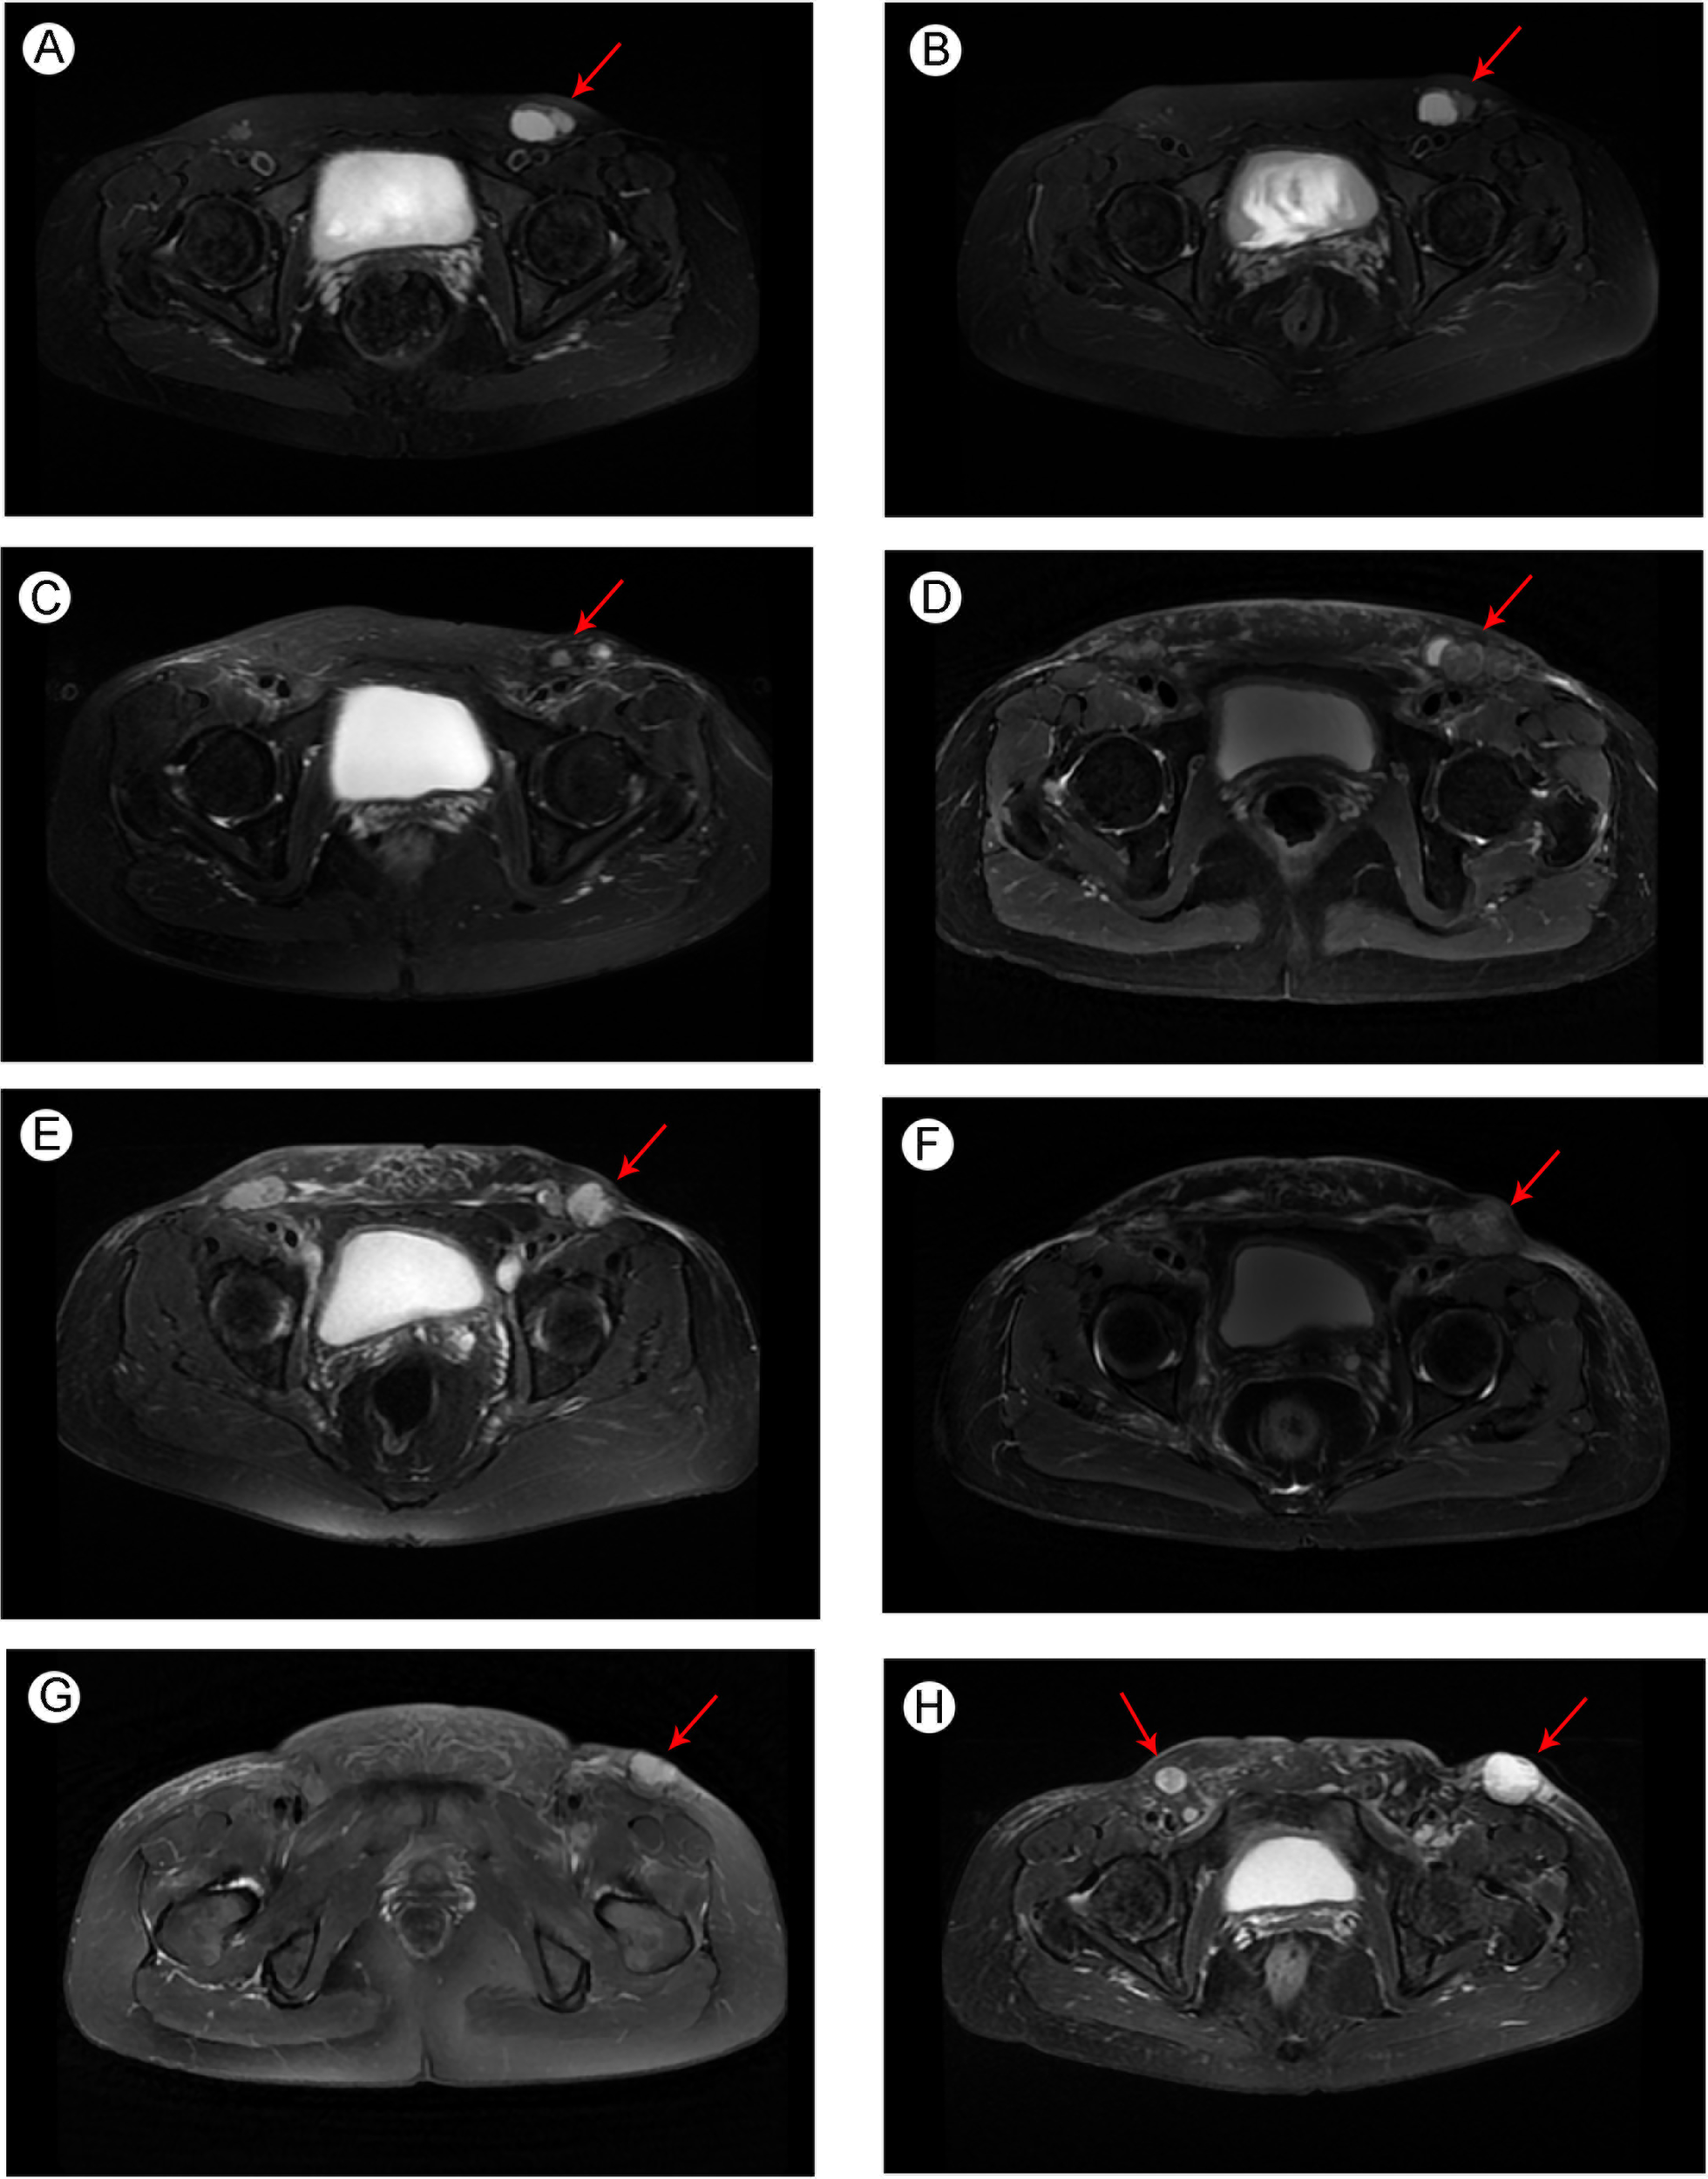

The patient had no previous medical history and no notable personal and family history. Physical examination revealed a palpable mass of about 4 × 2 cm in the left lower back and enlarged lymph nodes in the left groin. Laboratory tests showed that the complete blood count and blood biochemical indicators were basically within the normal range. A positron emission tomography/computed tomography (PET/CT) scan was done on 21 September 2018, and it revealed a malignant tumor that was located on the left lower back with right pelvic wall and bilateral inguinal lymph node metastasis (Figures 1A-C). Surgery was performed to remove the lesion on the left lower back on 25 September 2018 with a tumor-free margin. Pathological inspections confirmed the diagnosis of SGC, and immunohistochemistry results indicated that the mass was CK7+, P63+, CK5/6+, CK14+partial, GCDFP-15−, GATA-3−, p40−, and Ki-67 10% (Figures 2A-F). Her magnetic resonance (MR) scanning image on 12 October 2018 showed that the number of lymph nodes increased in the bilateral inguinal region, and the left one was enlarged, suggestive of malignant disease (Figure 3A). Because the left lesions were surgically unresectable, the patient agreed to undergo a cytotoxic chemotherapy regimen consisting of docetaxel and nedaplatin every 3 weeks for seven cycles. MRI revealed stabilization of the disease (Figure 3B). Then, she received intensity-modulated radiation therapy (IMRT) with 60 Gy to the gross tumor volume (GTV) and 50 Gy to the clinical tumor volume (CTV). After the radiotherapy, the patient was reviewed regularly, and the tumor size was obviously reduced (Figure 3C). However, MR scanning on 4 December 2019 revealed that the inguinal lymph nodes became larger (Figure 3D). We recommended that she undergo whole-genome sequencing. Due to the high price and limited specimen, only peripheral blood was used to detect PD-L1 expression. PD-L1 expression was 10%. Then, she underwent a chemotherapy and immunotherapy regimen consisting of albumin-bound paclitaxel and camrelizumab (a PD-1 inhibitor) for eight cycles. During the treatment, MRI showed stabilization of the disease (Figure 3E). On 14 December 2020, MR scanning showed that the number and size of the inguinal lymph nodes increased and were larger than the previous ones (Figures 3F, G). We repeatedly communicated with the patient about the treatment plan and told her that the prognosis was not good, but the patient still agreed to continue the treatment. Then, the patient underwent chemotherapy and immunotherapy with pemetrexed, nedaplatin, and camrelizumab for eight cycles. However, the inguinal lymph nodes were poorly controlled and growing larger according to the MRI result (Figure 3H). Then, the patient refused further treatment and went back home. Through telephone follow-up, we learned that the tumors in the left groin continued to grow and were ulcerating. The patient gradually developed pleural fluid and ascites. She died on 2 September 2021. To date, the survival time of this patient is 35 months. The timeline for treatments and efficacy evaluations in this case is summarized in Figure 4.

Figure 3

Pelvic MRI image of metastatic SGC (A) before docetaxel + nedaplatin treatment in October 2018; (B) after docetaxel + nedaplatin treatment in February 2019; (C) after the radiotherapy in September 2019; (D) before albumin-bound paclitaxel + camrelizumab treatment in December 2019; (E) after albumin-bound paclitaxel + camrelizumab treatment in September 2020; (F) before pemetrexed + nedaplatin + camrelizumab treatment in December 2020; and newly developed metastatic lymph nodes (G) before pemetrexed + nedaplatin + camrelizumab treatment in December 2020; (H) after pemetrexed + nedaplatin + camrelizumab treatment in March 2021. Arrows indicate the tumors in the groin region.